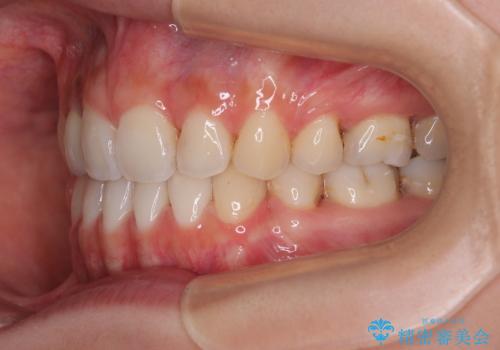

- 矯正装置

- クリアブラケット

- 前歯のデコボコと口元の突出感を気にして来院された患者様です。

口元の突出感が認められ、更には左右で異なる咬合状態であったため、下顎右側は第二小臼歯を、左側は第一小臼歯を抜去することでバランスを取るような治療計画としました。

下顎の抜歯位置を左右で変えることで、最終的に上下正中をほぼ一致させることができました。